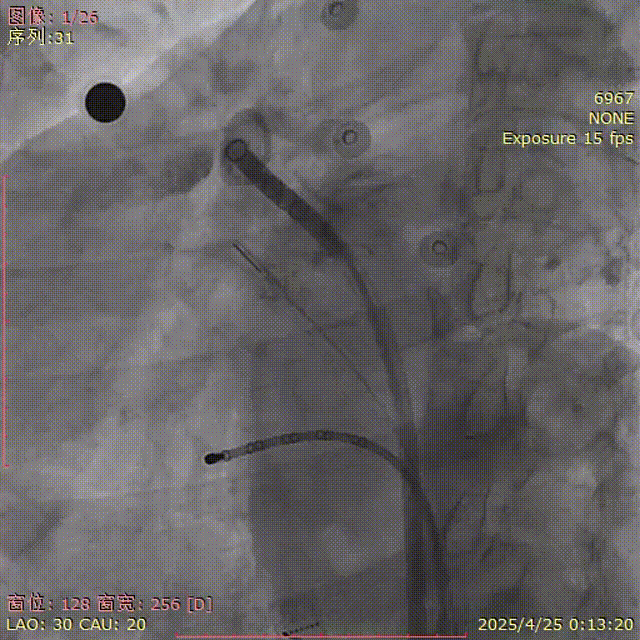

肩位造影

LAO 30° CRA 20°

肝位造影

LAO 30° CAU 20°